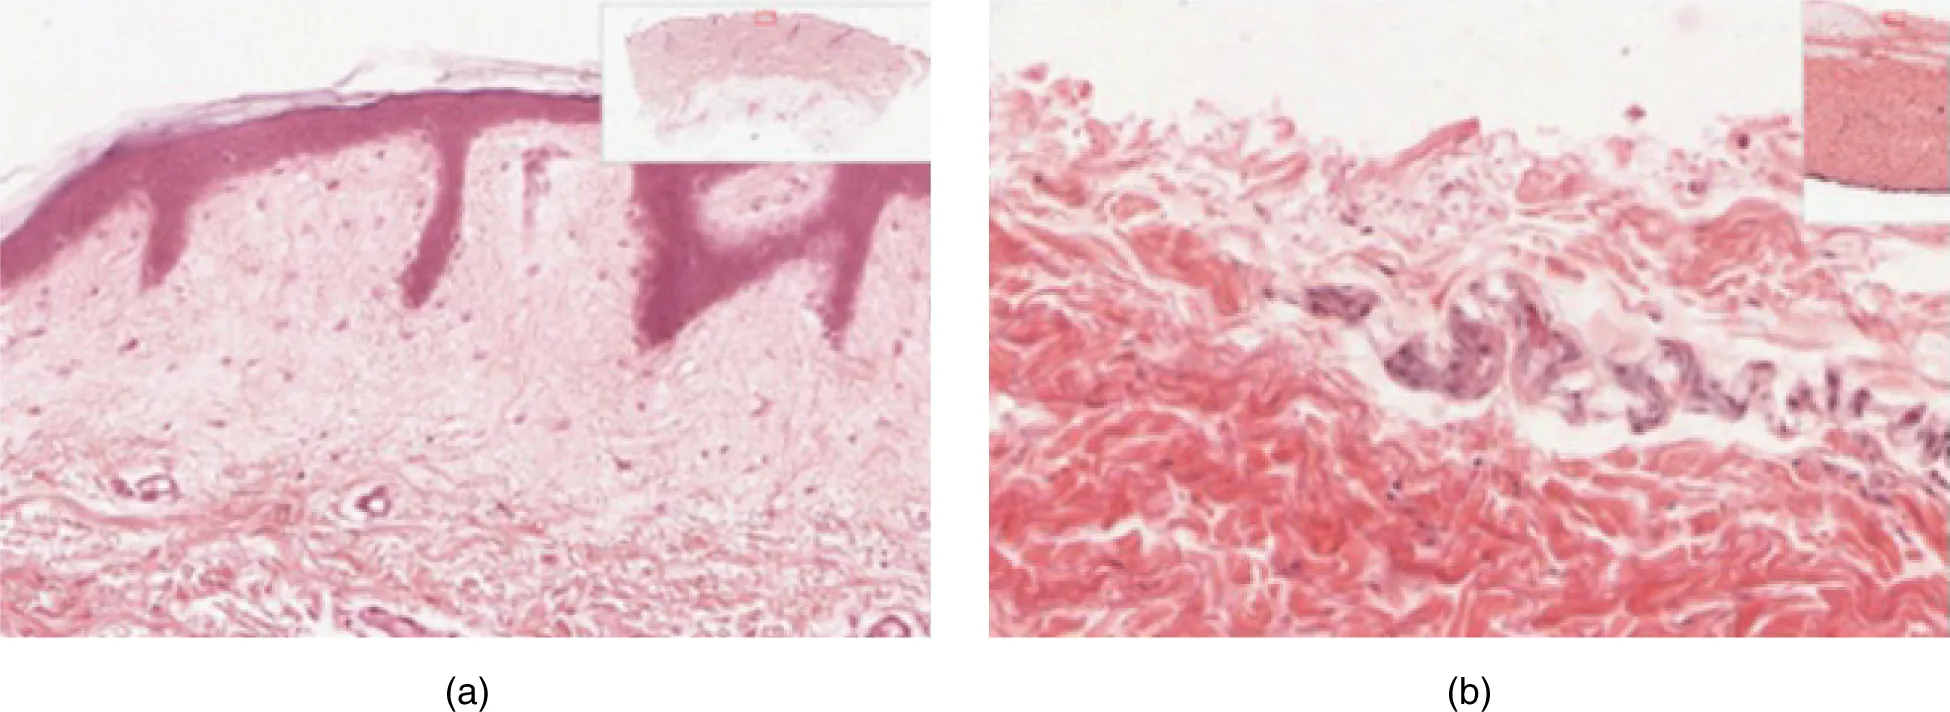

Dermis

The dermis might be considered the “core” of the integumentary system (derma- = “skin”), as distinct from the epidermis (epi- = “upon” or “over”) and hypodermis (hypo- = “below”). It contains blood and lymph vessels, nerves, and other structures, such as hair follicles and sweat glands. The dermis is made of two layers of connective tissue that compose an interconnected mesh of elastin and collagenous fibers, produced by fibroblasts (Figure 5.7).

This micrograph shows layers of skin in a cross section. The papillary layer of the dermis extends between the downward fingers of the darkly stained epidermis. The papillary layer appears finer than the reticular layer, consisting of smaller, densely-packed fibers. The reticular layer is three times thicker than the papillary layer and contains larger, thicker fibers. The fibers seem more loosely packed than those of the papillary layer, with some separated by empty spaces. Both layers of the dermis contain cells with darkly stained nuclei.

Figure 5.7 Layers of the Dermis This stained slide shows the two components of the dermis—the papillary layer and the reticular layer. Both are made of connective tissue with fibers of collagen extending from one to the other, making the border between the two somewhat indistinct. The dermal papillae extending into the epidermis belong to the papillary layer, whereas the dense collagen fiber bundles below belong to the reticular layer. LM × 10. (credit: modification of work by “kilbad”/Wikimedia Commons)

Papillary Layer

The papillary layer is made of loose, areolar connective tissue, which means the collagen and elastin fibers of this layer form a loose mesh. This superficial layer of the dermis projects into the stratum basale of the epidermis to form finger-like dermal papillae (see Figure 5.7). Within the papillary layer are fibroblasts, a small number of fat cells (adipocytes), and an abundance of small blood vessels. In addition, the papillary layer contains phagocytes, defensive cells that help fight bacteria or other infections that have breached the skin. This layer also contains lymphatic capillaries, nerve fibers, and touch receptors called the Meissner corpuscles.

Reticular Layer

Underlying the papillary layer is the much thicker reticular layer, composed of dense, irregular connective tissue. This layer is well vascularized and has a rich sensory and sympathetic nerve supply. The reticular layer appears reticulated (net-like) due to a tight meshwork of fibers. Elastin fibers provide some elasticity to the skin, enabling movement. Collagen fibers provide structure and tensile strength, with strands of collagen extending into both the papillary layer and the hypodermis. In addition, collagen binds water to keep the skin hydrated. Collagen injections and Retin-A creams help restore skin turgor by either introducing collagen externally or stimulating blood flow and repair of the dermis, respectively.